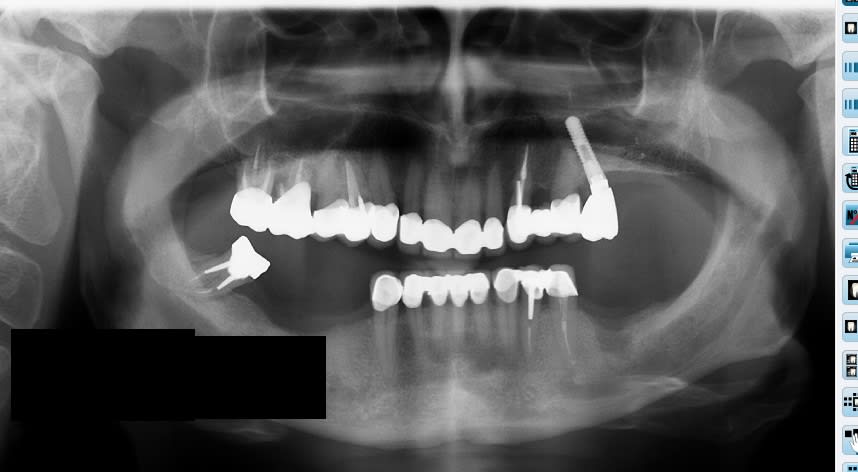

La fin.

Petite image paro sur 16 qui n'était pas là en 2017.

Pano hnxsux - Eugenol

Sans déconner :-)la 47 , une tueuse :-))

Et merde, jte jure elle accroche dans aucun mouvement, je suis deg, c'est tellement évident.